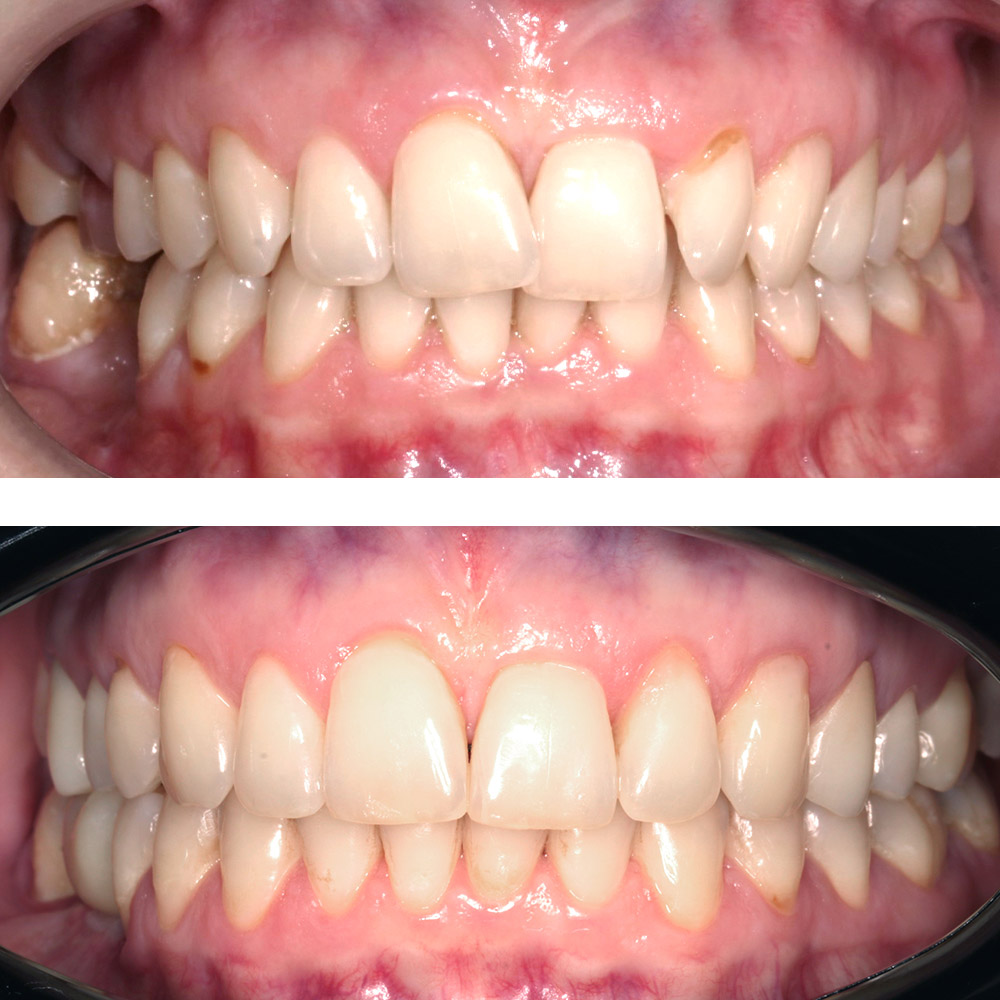

Кейс 21

ДО

ПОСЛЕ